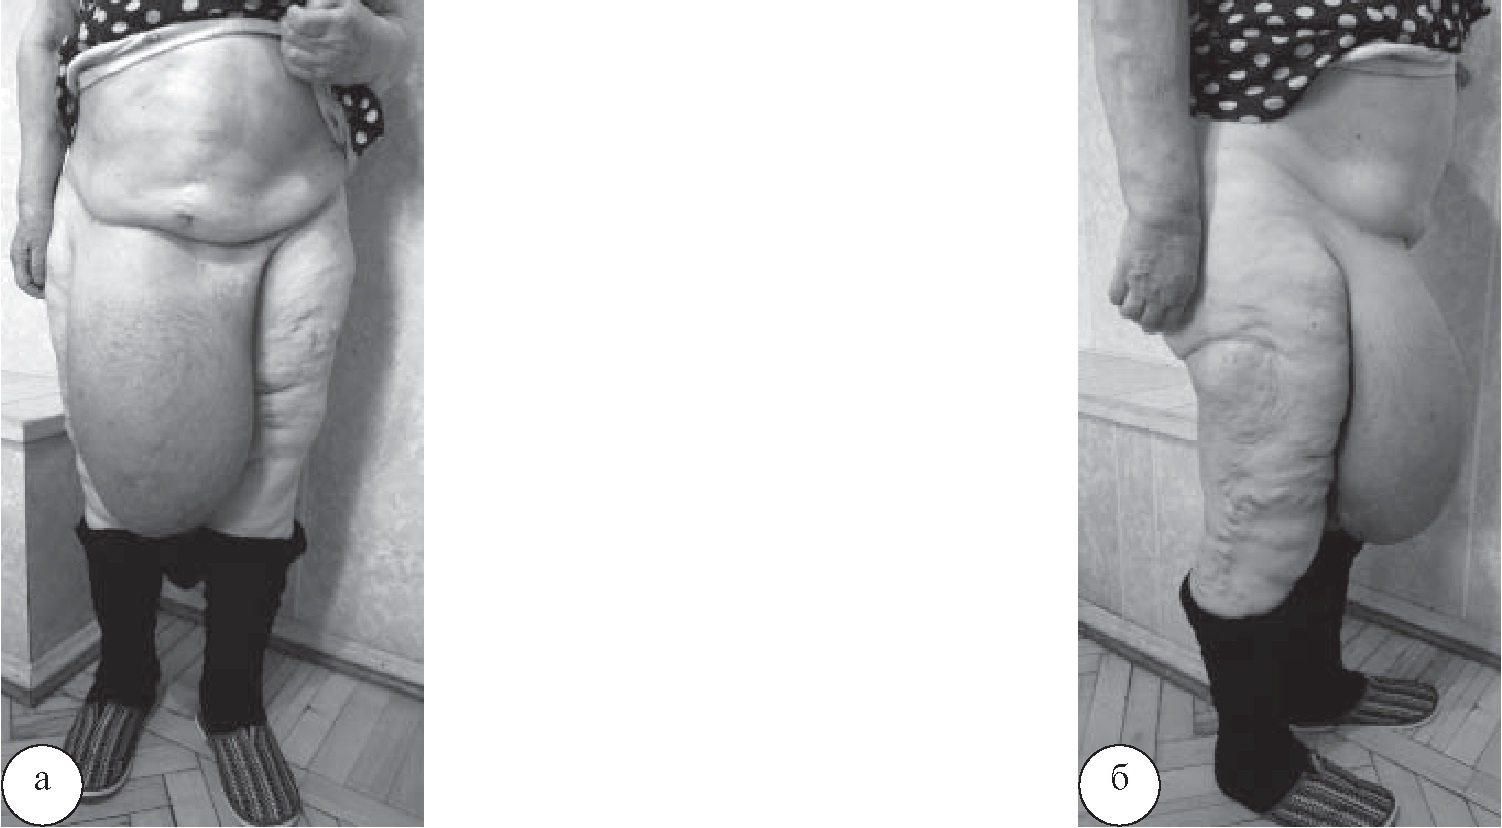

В правой паховой области параллельно паховой связке выполнен разрез длиной 18 см. Послойно рассечены мягкие ткани и апоневроз наружной косой мышцы живота, выделен и вскрыт грыжевой мешок размерами 44×25 см. Его содержимым являлись петли тонкой кишки протяженностью около 1,5 м, слепая кишка с червеобразным отростком, участок восходящего отдела ободочной кишки (рис. 2).

Рис. 2. Содержимое грыжевого мешка